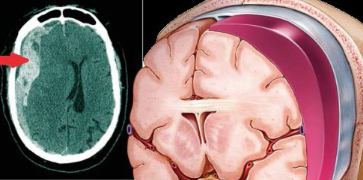

Você já ouviu falar em tratamento clínico e por cateterismo para o hematoma subdural crônico?

O hematoma subdural crônico é uma das doenças mais frequentes da Neurocirurgia que afeta geralmente pacientes com idade superior à 65 anos de idade. A sua ocorrência tem aumentado nos últimos anos, em virtude do envelhecimento da população e da utilização disseminada...